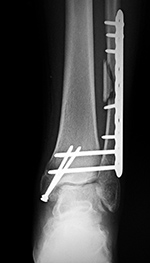

Dynamic compression plate and syndesmotic screws as well as two fully threaded cortical medial malleolus screws

|